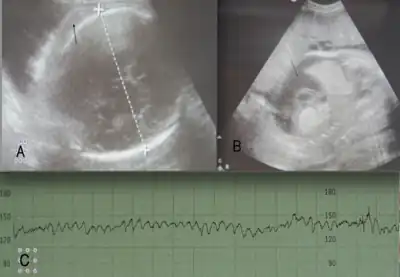

Symptoms of Rh disease include yellowish amniotic fluid and enlarged spleen, liver or heart or buildup of fluid in the abdomen of the fetus.[9]

- Once the titer of anti-D reaches a certain threshold (normally 8 to 16), serial Ultrasound and Doppler examinations are performed to detect signs of fetal anemia

- Detection of increased blood flow velocities in the fetus are a surrogate marker for fetal anemia that may require more invasive intervention

- If the flow velocity is found to be elevated a determination of the severity of anemia needs to ensue to determine if an intrauterine transfusion is necessary

- This is normally done with a procedure called percutaneous umbilical cord blood sampling (PUBS or cordocentesis) [19]